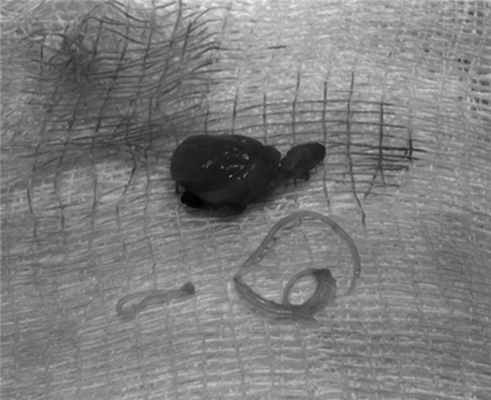

Выполнено оперативное вмешательство - иссечение новообразования в пределах здоровых тканей. Интраоперационно диагноз подтвержден - удаленное новообразование плотной консистенции, на разрезе стенка толщиной до 2 мм, в просвете мутная жидкость, а также нитчатое образование (гельминт) диаметром до 1 мм, длиной до 9 см (рис. 1).

Рис. 1. Удаленный паразит с оболочкой.

Выполнено оперативное вмешательство - иссечение новообразования в пределах здоровых тканей. Интраоперационно диагноз подтвержден - удаленное новообразование плотной консистенции, на разрезе капсула толщиной до 3 мм, в просвете мутная жидкость, а также нитчатое образование (гельминт), подвижное, диаметром до 1 мм, длиной до 12 см (рис. 3).

Рис. 3. Макроскопическая картина удаленного паразита.

При гистологическом исследовании стенок гранулемы в двух наблюдениях - обнаружена фиброзная ткань. В Ростовском НИИ микробиологии и паразитологии Роспотребнадзора проведено паразитологическое исследование непосредственно гельминта, его результат - неоплодотворенная самка Dirofilaria repens длиной 12 см. Итак, проведена до- и послеоперационная диагностика дирофиляриоза.